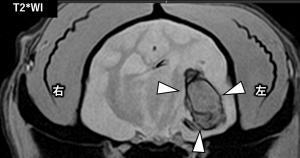

セイタの脳のMRI画像

「セイタ」の脳のMRI画像 矢頭:左大脳の出血(黒っぽい領域)

・左大脳の出血と周囲の脳浮腫